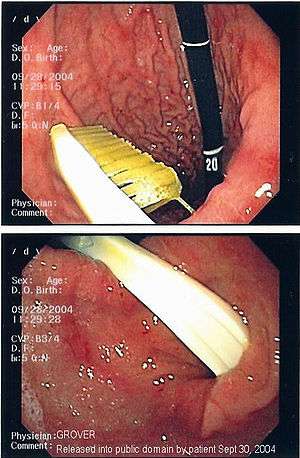

Endoscopic retrieval involves the use of a gastroscope or an optic fiber charge-coupled device camera. This instrument is shaped as a long tube, which is inserted through the mouth into the esophagus and stomach to identify the foreign body or bodies. This procedure is typically performed under conscious sedation. Many techniques have been described to remove foreign bodies from the stomach and esophagus. Usually the esophagus is protected with an overtube (a plastic tube of varying length), through which the gastroscope and retrieved objects are passed.[11]

Once the foreign body has been identified with the gastroscope, various devices can be passed through the gastroscope to grasp or manipulate the foreign body. Devices used include forceps, which come in varying shapes, sizes and grips,[12] snares, and oval loops that can be retracted from outside the gastroscope to lasso objects,[13] as well as Roth baskets (mesh nets that can be closed to trap small objects),[14] and magnets placed at the end of the scope or at the end of orogastric tubes.[12][15] Some techniques have been described that use foley catheters to trap objects, or use two snares to orient foreign bodies.[6]